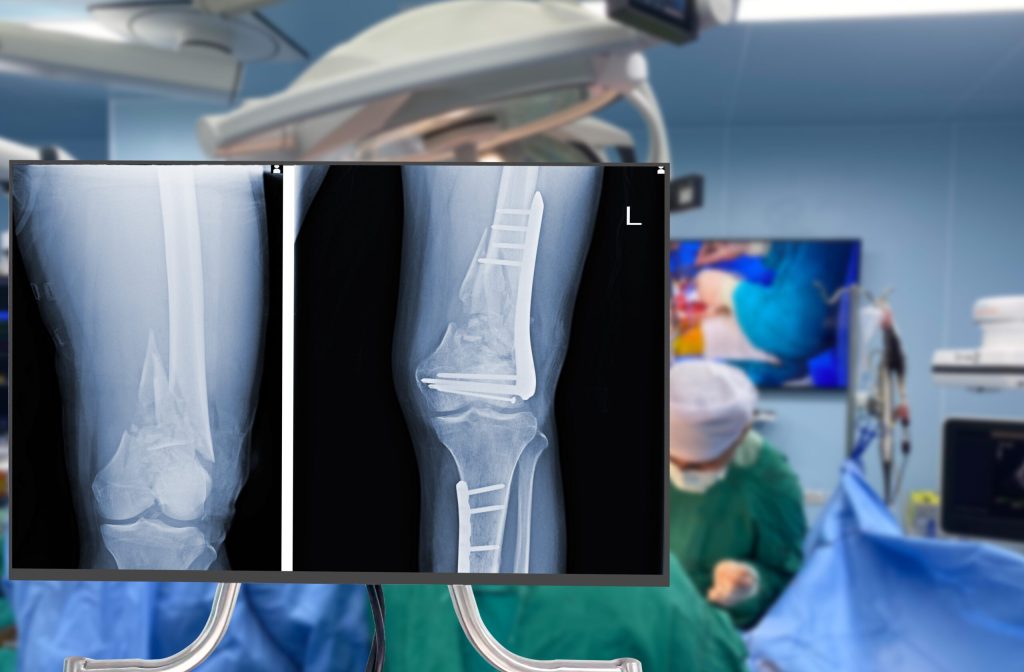

L’orthopédie-traumatologie est la chirurgie du système musculosquelettique : os, articulations, cartilages, tendons, ligaments et nerfs périphériques. Elle s’articule autour de deux registres complémentaires.

La traumatologie prend en charge les urgences : fractures, luxations, plaies tendineuses, traumatismes du rachis, polytraumatismes. C’est la médecine des situations critiques où la rapidité et la justesse du geste chirurgical peuvent conditionner la survie ou la récupération fonctionnelle.

L’orthopédie programmée couvre les arthroplasties (prothèses de hanche, de genou), la chirurgie rachidienne (hernies discales, déformations), l’arthroscopie, l’oncologie osseuse et l’orthopédie pédiatrique. C’est une médecine de reconstruction et d’amélioration de la qualité de vie, souvent auprès de patients âgés ou porteurs de pathologies chroniques.

L’orthopédie « froide » comprend les arthroplasties (hanche, genou), la chirurgie rachidienne (herniectomies, arthrodèses, décompressions), l’arthroscopie (genou, épaule, cheville) et la chirurgie pédiatrique. Ces interventions exigent une précision technique, une maîtrise de l’instrumentation et une bonne compréhension de la biomécanique articulaire.

Dextérité chirurgicale et sens mécanique. L’orthopédie requiert une gestuelle précise, une résistance physique au bloc opératoire, et une vision tridimensionnelle de l’anatomie. Comprendre comment un implant interagit avec un os, comment répartir les contraintes — c’est une compétence qui se construit progressivement mais qui doit venir naturellement.

Prise de décision rapide. En traumatologie d’urgence, le timing chirurgical est déterminant : opérer immédiatement ou stabiliser d’abord, choisir la technique d’ostéosynthèse adaptée, gérer les complications peropératoires. Ces décisions doivent être prises vite et correctement.